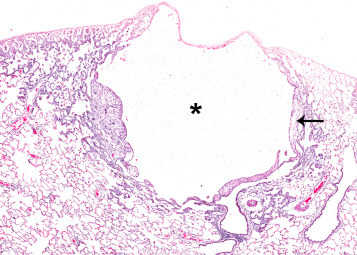

3. Congenital Lesions

Congenital lesions of the lung are rare. Simple cysts are an incidental finding (Figure 23.7 ). They may be subpleural, cause minimal compression of the adjacent parenchyma, and have some fibrosis in the wall. Frequently they do not have a distinct epithelial cell layer in the wall and are lined by fibrous tissue. It is not known whether these lesions are present from birth or whether they arise later as a result of airway obstruction. The latter would not be considered congenital lesions.

Figure 23.7.

Subpleural cyst (asterisk) with mild fibrosis (arrow) in the cyst wall.